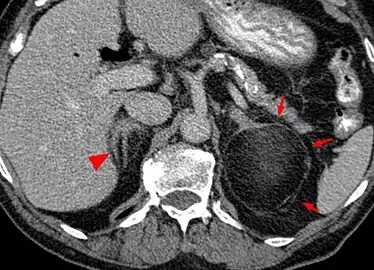

Myeloplipoma shown on a CT scan image -

a)CT scan showing heterogeneous bilateral myelolipomas b) macroscopic aspect of left adrenal myelolipomas

Most myelolipomas are unexpected findings on CT scans and MRI scans of the abdomen. They may sometimes be seen on a plain X-ray films.[4]